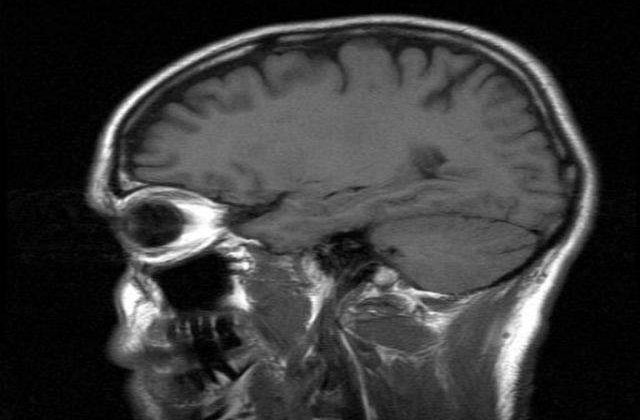

Intr-o serie de experimente pe sobolani, cercetatorii de la Imperial College din Londra au descoperit un mecanism care pare sa "simta" cat de multa glucoza ajunge la creier si determina animalele sa caute o sursa suplimentara de glucoza in cazul in care detecteaza un deficit. In cazul oamenilor, ar putea avea un rol in controlarea nevoii de dulciuri si alimente bogate in amidon.

Glucoza, o componenta a carbohidratilor, este principala sursa de energie utilizata de neuroni.

Echipa de cercetatori a pornit de la o ipoteza potrivit careia o enzima, numita glucokinaza, implicata in procesul de detectare a glucozei in ficat si pancreas, ar putea avea un rol in controlarea dorintei privind aportul de glucoza. Glucokinaza se gaseste in hipotalamus, parte a creierului care controleaza mai multe functii, printre care si aportul de hrana, scrie MEDIAFAX.